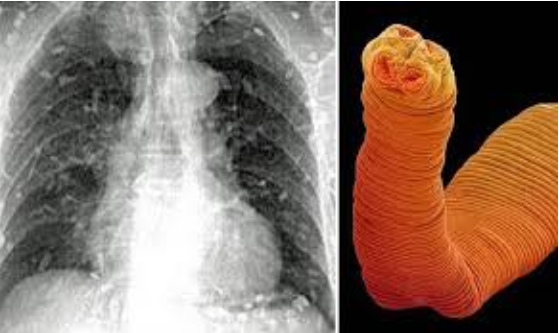

Mans entire body flooded with worms after eating sushi 2.png

Mans entire body flooded with worms after eating sushi 2.png (311.45 KiB) Viewed 24378 times

All fish contain a worm called Diphyllobothrium, it is a type of worm that can cause a disease known as Diphyllobothriasis upon consumption of raw or undercooked fish. The symptoms if they occur include abdominal discomfort or pain, Diarrhea, weakness, and weight loss. Yes, it can be fatal if the worms were to reach the brain. Once a human becomes infected, a tape worm will grow, and can survive for several years, while going undetected for several weeks or months.

Tapeworm infections occur after ingesting the larvae of diphyllobothrium, found in freshwater fish such as salmon, although marinated and smoked fish can also transmit the worm.